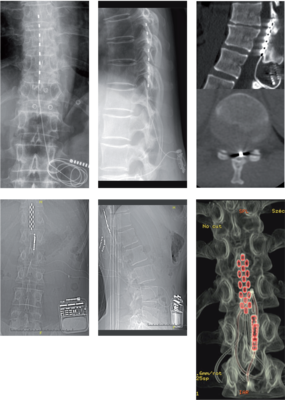

- Gerincvelői stimuláció (spinal cord stimulation, SCS). Alsó és felső végtagi neuropathiás fájdalmak csökkentésében hatásos. Az elektródát dorsalisan ültetjük be az epiduralis térbe, abba a gerincvelői szegmentumba, amelyikből a fájdalmas dermatomát beidegző ideggyökök erednek. Az elektródákat perkután módszerrel vagy sebészi laminotomiás feltárásból juttatjuk be az epiduralis térbe. A stimuláció során a felszálló vastag érzőpályákat (Goll és Burdach) ingereljük, aminek következtében a fájdalmas dermatomában az égő, zsibbadó fájdalom helyett kellemes, bizsergő érzés alakul ki. A perkután elektródák hatásosak a dermatomalis fájdalom kezelésében, mert vékonyak, és kisebb terület ingerlésére képesek. Komplexebb, több dermatomát érintő végtagi és derékfájdalom esetén a sebészi elektródák eredményesek, mert szélesebb lefedettséget biztosítanak (10–11. ábra). A fájdalomcsillapító hatást a kapukontroll-elmélettel magyarázzák. A műtét indikációja a végtagi neuropathiás fájdalom, a beteg kompenzált pszichés állapota és a gyógyszeres kezelés hatástalansága.11. ábra. Fent az epiduralis térbe ültetett perkután SCS-elektróda látható az AP (bal) és az oldalirányú (középső) röntgenképeken, valamint a sagittalis (jobb felső) és az axialis (jobb alsó)CT-képen. Lent sebészi SCS-elektróda (5-6-5 kontaktos) és a stimulátor figyelhető meg az AP (bal) és az oldalirányú (középső) röntgenképeken, valamint a 3 dimenzióban rekonstruált CT- (jobb) felvételen